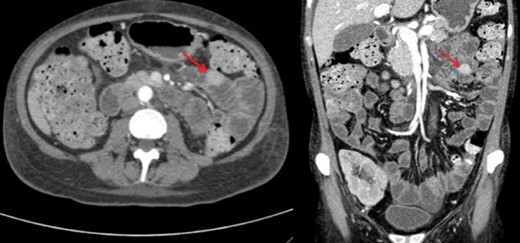

A renal biopsy was performed and showed atypical glomerulopathy with immune complexes. An autoimmune panel was negative. Investigations were performed to assess the presence of an inflammatory or infectious process. An abdominopelvic computed tomography (CT) scan revealed a hyperdense mass in the small bowel (Fig. 1). CT enterography further showed a 2 cm homogeneous jejunal lesion with no extraluminal extension (Fig. 2). Positron emission tomography scan displayed no hypermetabolism in the small bowel or in the renal allograft. Differential diagnosis included gastrointestinal stromal tumor and leiomyoma, but due to the transplant immunosuppression and the Epstein-Barr viral load of 16 596 copy/mL, a post-transplant lymphoproliferative disease (PTLD) was highly suspected.

The patient’s lesion was big enough to be detected on CT imaging, whereas usual ectopic pancreatic rests usually present as smaller hardly noticeable nodules located in the distal stomach, duodenum, proximal jejunum, or even the gallbladder and bile ducts [2]. They are typically discovered incidentally during endoscopy, surgery or autopsy. CT findings that may help differentiate ectopic pancreatic tissue from other submucosal lesions include a flat-ovoid shape, a location in the antrum, pylorus or duodenum, an endoluminal growth pattern with an ill-defined border and a prominent enhancement of the overlying mucosa [3]. Kim et al. [3] found that the presence of at least two of the above findings had a sensitivity of 100% and a specificity of 82.5% for diagnosing a pancreatic rest in the upper gastrointestinal tract. Nonetheless, radiological diagnosis remains a challenge as shown in this case. None of the above CT signs were specifically described to suggest a pancreatic rest rather that a neoplastic process.